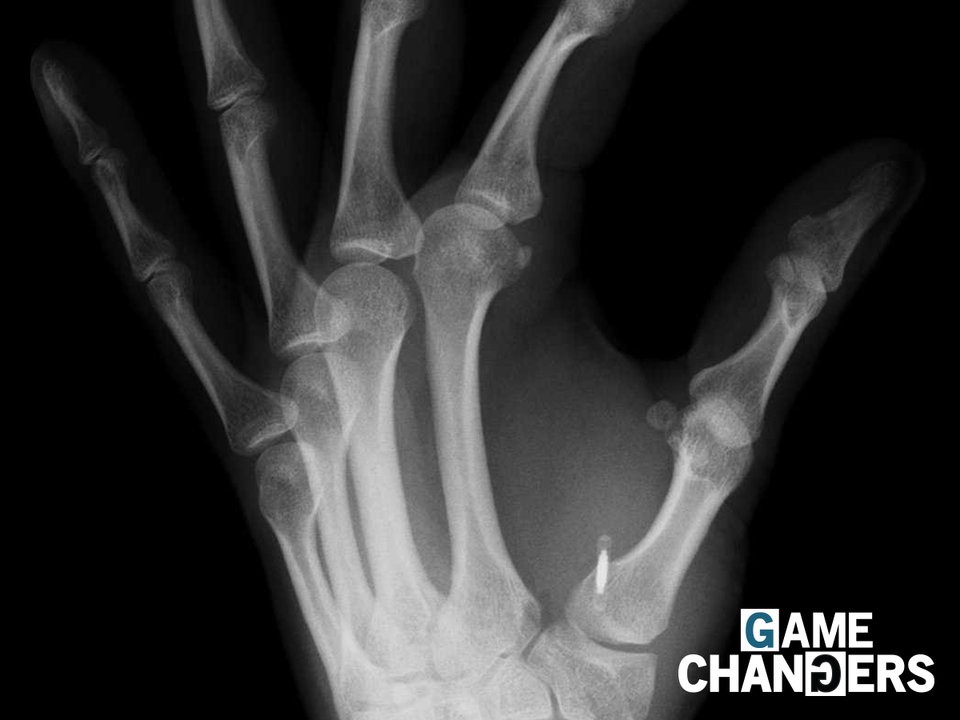

Có kích thước bằng hạt gạo, con chíp này được dùng thay cho thẻ căn cước, thẻ vào cửa hay thậm chí vé tàu

Hàng nghìn người người tại Thụy Điển đã tiến hành cấy con chíp vào cơ thể để thay cho các loại thẻ bao gồm thẻ căn cước hay thậm chí vé tàu.

Theo Agence France-Presse, đã có khoảng 3.000 người Thụy Điển cấy con chíp - có kích thước bằng hạt gạo, kể từ khi công nghệ này lần đầu tiên được đưa vào ứng dụng tại quốc gia này vào năm 2015.

Con chíp dưới da đã giúp thay thế cho các loại thể cần thiết cho nhu cầu hàng ngày của người dân.

Bản chụp X quang bàn tay có gắn con chíp - Ảnh: Business Insider.